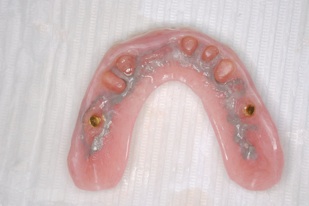

この方は結局、all on 4 を応用し、奥歯に両側2本のインプラントを傾斜埋入して、それにマグネットをつけました。これなら骨移植をせずにインプラントが可能になり、3ヶ月ほどで終了できます。

マグネットをつけているので大幅に義歯の面積を縮小することが可能になりました。